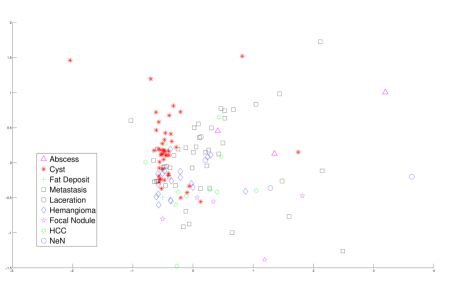

For the purpose of building intuition, we used classical multidimensional scaling (CMDS) on the distance matrix, using the above feature vectors as columns, to produce 2D and 3D visualizations of the lesions, shown in Figure 6. Note that the axes simply give the coordinates of the embedding given by CMDS and that the vertical axis in Figure 6(b) is pointed at the reader in Figure 6(a).